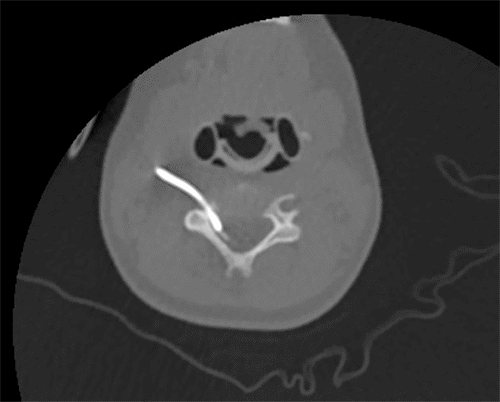

After the procedure, a chest X ray (Figure 1) confirmed the seemingly successful placement of the CVC chemo-port; the patient was transferred to the pediatrics team for postoperative monitoring. Over the next few days, the port never functioned correctly. A minimal amount of blood was able to be aspirated from the port. While it seemed to flush well, the patient would complain of severe pain when normal saline flush was injected through the port. The pain was described as being all over her body. She could not be distracted from the pain, which reportedly stopped as soon as the flush was stopped. Although no IV medication was ever administered through the port, injection of TPA was performed through the port due to a concern of sluggish blood draw from the port, which did not improve with a blood draw. Due to concern for a malpositioned port, interventional radiology was consulted and performed a port contrast study (Figure 2 and Figure 3) which revealed that the catheter was located in the epidural space, which was confirmed by a CT scan (Figure 4). The port was immediately removed while the patient was sedated in the radiology suite.

Figure 4. CT Confirmation of Epidural Space Displacement. Published with Permission

Arrow denotes catheter tip in epidural space, confirming result of contrasted port study.